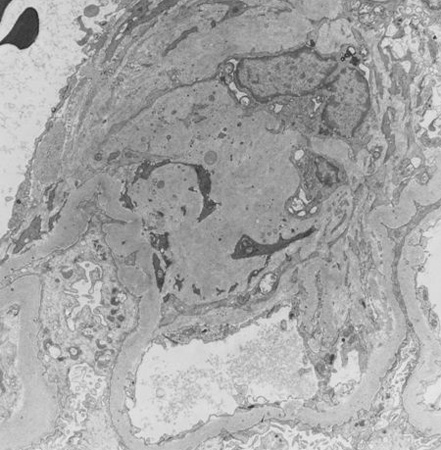

Diabetes mellitus is characterised by high glucose levels and increased glomerular pressure, both of which can cause glomerular mesangium expansion via increased mesangial stretch. Platelet-derived growth factor (PDGF) and transforming growth factor-beta (TGF-beta) mediate mesangial expansion and fibrosis via the stimulation of matrix protein (collagen and fibronectin) synthesis and decreased matrix degradation. Glucose forms advanced glycation end products (AGEs) by binding irreversibly to proteins. Over years, AGEs form crosslinks, stimulate the release of growth factors such as TGF-beta, and cause fibrosis. Angiotensin II (ATII), elevated in DKD, constricts the efferent arteriole in the glomerulus, causing high glomerular capillary pressures, and also stimulates fibrosis and glomerular inflammation. Mesangial expansion is characteristic of early diabetic glomerulosclerosis and is followed by fibrosis in the late stages. Kimmelstiel-Wilson nodules, areas of mesangial expansion on biopsy, are the hallmark of diabetic glomerulosclerosis and are seen in half of the cases of DKD. Increased glomerular basement membrane width, diffuse mesangial sclerosis, hyalinosis, microaneurysm, and hyaline arteriosclerosis are present in addition to tubular and interstitial changes.[17] Hypertension, via mesangial stretch, can aggravate progression of DKD.[Figure caption and citation for the preceding image starts]: Diabetic kidney disease: mesangial expansion due to increased mesangial matrix and decreased degradation of glycosylated collagenFrom the collection of Dr Raoul Fresco; used with permission [Citation ends].

[Figure caption and citation for the preceding image starts]: Diabetic kidney disease: mesangial expansion is usually recognised when it has exceeded 1.5 times the normal mesangial matrixFrom the collection of Dr Raoul Fresco; used with permission [Citation ends].